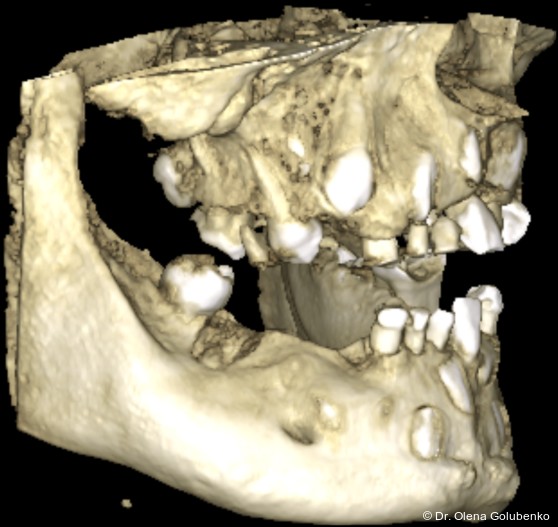

Die dreidimensionale Bildgebung zeigt meist eine hohe Anzahl nicht durchgebrochener permanenter und überzähliger Zähne, die in unterschiedlicher Lage im Kiefer verbleiben (Abb. 3+4).

Die Diagnostik der cleidokranialen Dysplasie basiert auf einer sorgfältigen klinischen Untersuchung, der Analyse von Panoramaaufnahmen sowie insbesondere auf der digitalen Volumentomografie (DVT). Ziel ist es, die Anzahl, Lage, den Entwicklungsstand sowie mög­liche Interferenzen der retinierten und überzähligen Zähne präzise zu erfassen und in ei­nen funktionellen sowie skelettalen Kontext einzuordnen (Abb. 5–8).

• ausgeprägte dentale Anomalien (Abb. 2)